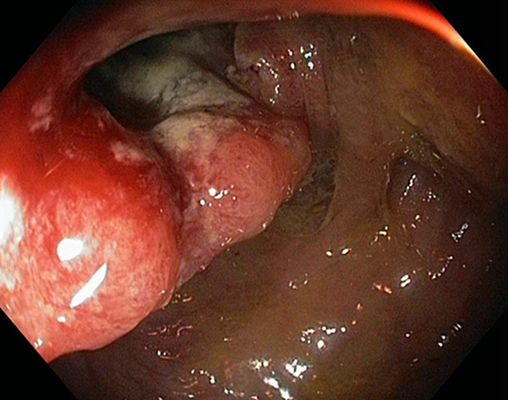

結腸癌症狀 (7)

結腸癌症狀 (8)

結腸癌症狀 (9)

結腸癌症狀 (49)

結腸癌症狀 (5)

結腸癌症狀 (50)

結腸癌症狀 (51)

結腸癌症狀 (6)